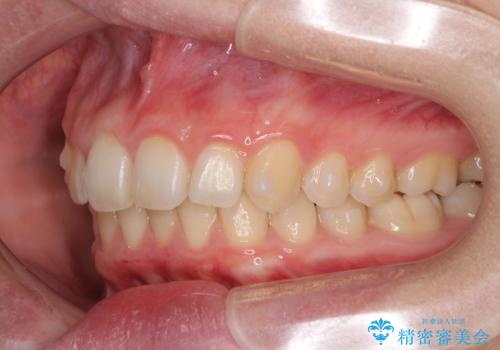

- 八重歯を気にして来院された患者様です。

八重歯の後ろの歯を1歯抜歯し、補助装置(リンガルアーチ)を用いて八重歯の位置を改善し、その後インビザラインにより矯正治療を行うこととしました。

下顎前歯が1本欠損したスリーインサイザーという状態であるため、上下の前歯の咬み込みが深くなったり、奥歯の咬み合わせが理想的なものとならなかったりという仕上がりになってしまいます。

前歯の見た目や奥歯の咬み合わせに、患者様が違和感を感じない状態として治療を終えました。